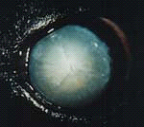

A cataract is any opacity within a lens. The opacity can be very small (incipient cataract) and not interfere with vision. It can involve more of the lens (immature cataract) and cause blurred vision. Eventually, the entire lens can become cloudy, and all functional vision lost. This is called a mature cataract. Some mature cataracts will transform over time into hyper mature cataracts.

Immature, mature, and hyper mature cataracts can cause a serious reactive inflammation inside the eye (Lens Induced uveitis, that must be medically treated, It can lead to complications such as glaucoma or a detached retina if cataract surgery is not performed, and This uveitis decreases the success rate of cataract surgery.

In dog with diabetes, cataracts develop very fast and they can lead to medical and surgical emergency. Once a lens has developed a cataract, it should removed surgically. cataract surgery is extremely delicate surgery and is performed under general anesthesia with high-magnification using an operating microscope. Some dogs require anti-inflammatory medication for several weeks, months, or lifetime following cataract surgery.